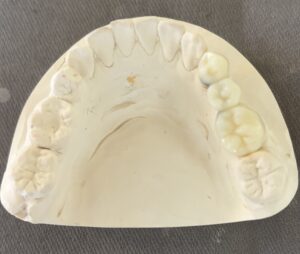

上顎 は 完璧 なん です

下顎 に 少し 【スペース】が 生じました。

ご覧 の 通り

スペース が 狭すぎる の です。

完成した クラウン修復 は 【違和感】 ある くらい

小さな 【歯】に なって しまいます。

私は ブリッジ修復 を 選択しました。

歯科技工 は モチロン  石三くん です。

違和感ない 形態で 仮歯を 創って くれました。